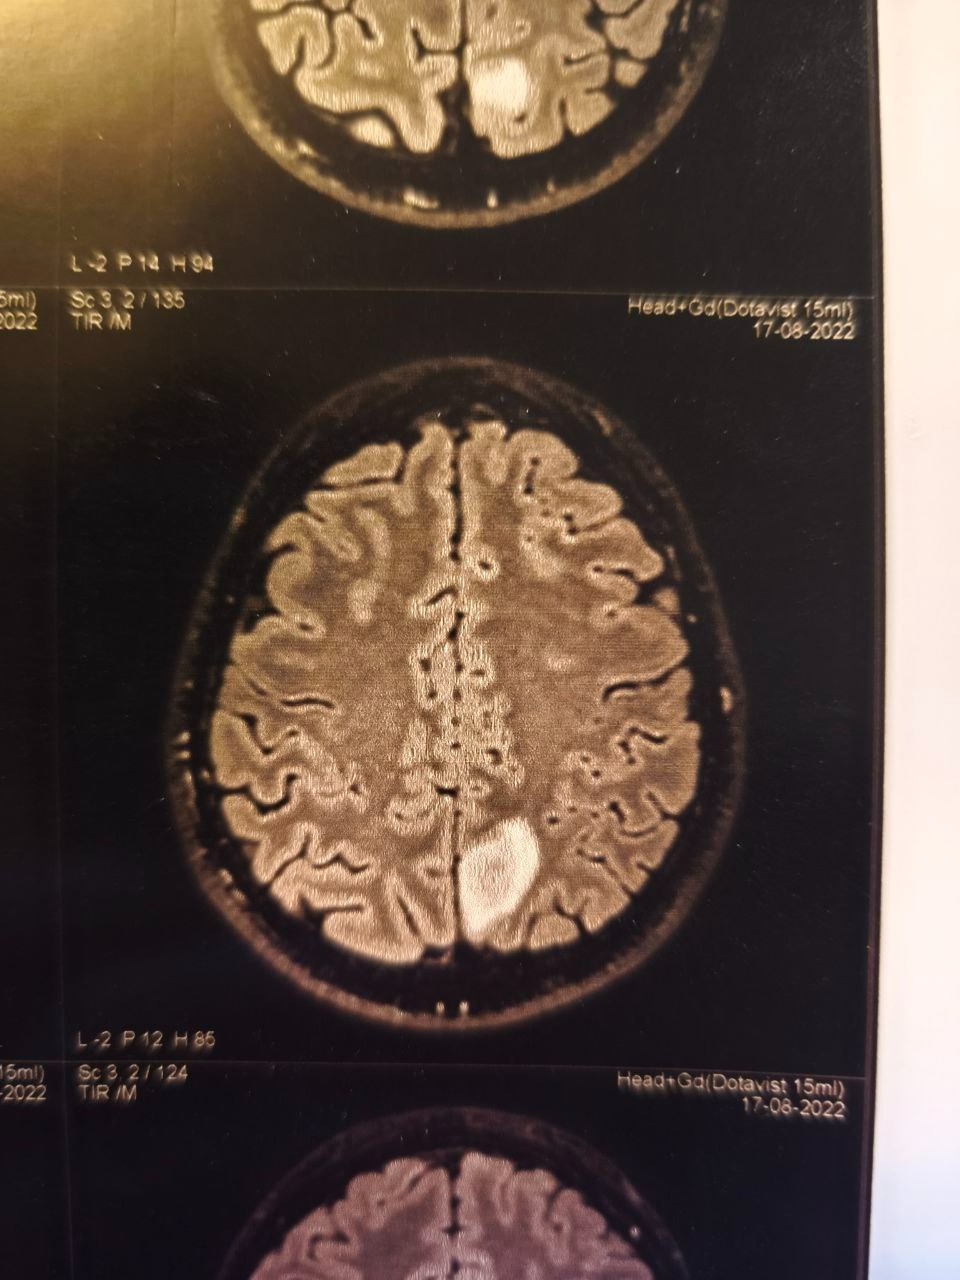

In early 2025, at just 39 years old, Vladimir was diagnosed with an aggressive Grade IV astrocytoma (glioblastoma) brain tumour — one of the most aggressive forms of brain cancer. He has already undergone major brain surgery and now faces months of radiation, chemotherapy, and recovery with uncertain outcomes and potential long-term effects.